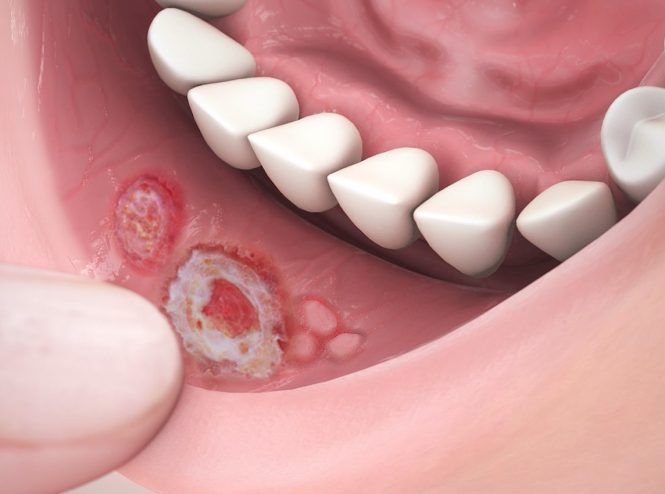

بیماری های دهان و دندان چیست؟ بیماریهای دهان و دندان شامل مجموعهای از اختلالات و آفاتی است که…

آبسه دندان چیست؟ آبسه دندان یک وضعیت التهابی است که در نتیجه عفونت دندان، زخم دهان یا مشکلات…